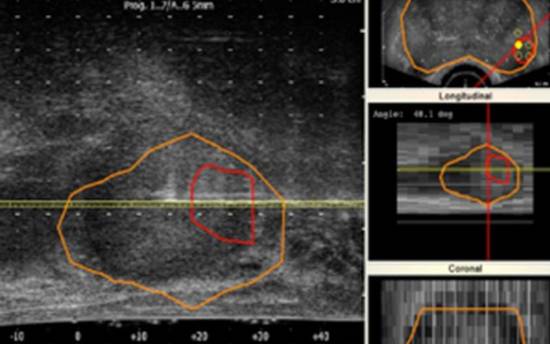

En este sentido, recientemente se ha introducido una nueva herramienta en el quirófano que ofrece imágenes en tiempo real y, al mismo tiempo, permite una mejor selección de tejidos para la biopsia. Los resultados tienen una mayor sensibilidad y precisión, cercana al 100%. Esto se consigue por combinación de la resonancia magnética de próstata multiparamétrica (RMmp) con la ecografía convencional.

La unión de estas dos técnicas permite mejorar, a su vez, el procedimiento habitual de la biopsia prostática ya que ofrece una selección más precisa de los tejidos susceptibles de ser tumores de alto riesgo, que son los que necesitan una terapia y una posible intervención.

El doctor Miguel Sánchez Encinas, jefe del Servicio de Urología del Hospital Universitario Rey Juan CarlosUrologíaUrología , nos explica que: "la resonancia magnética de próstata multiparamétrica combina diferentes secuencias anatómicas y funcionales, permitiendo identificar por imagen aquellas zonas con riesgo elevado de ser tumores con significación clínica".

Acerca de los resultados obtenidos, nuestro doctor detalla que "se consigue aumentar la precisión diagnóstica llegando a una sensibilidad del 92%, superior a la obtenida con ecografía convencional". Y todo esto se logra en tiempo real en el mismo momento en el que el paciente está en el quirófano.